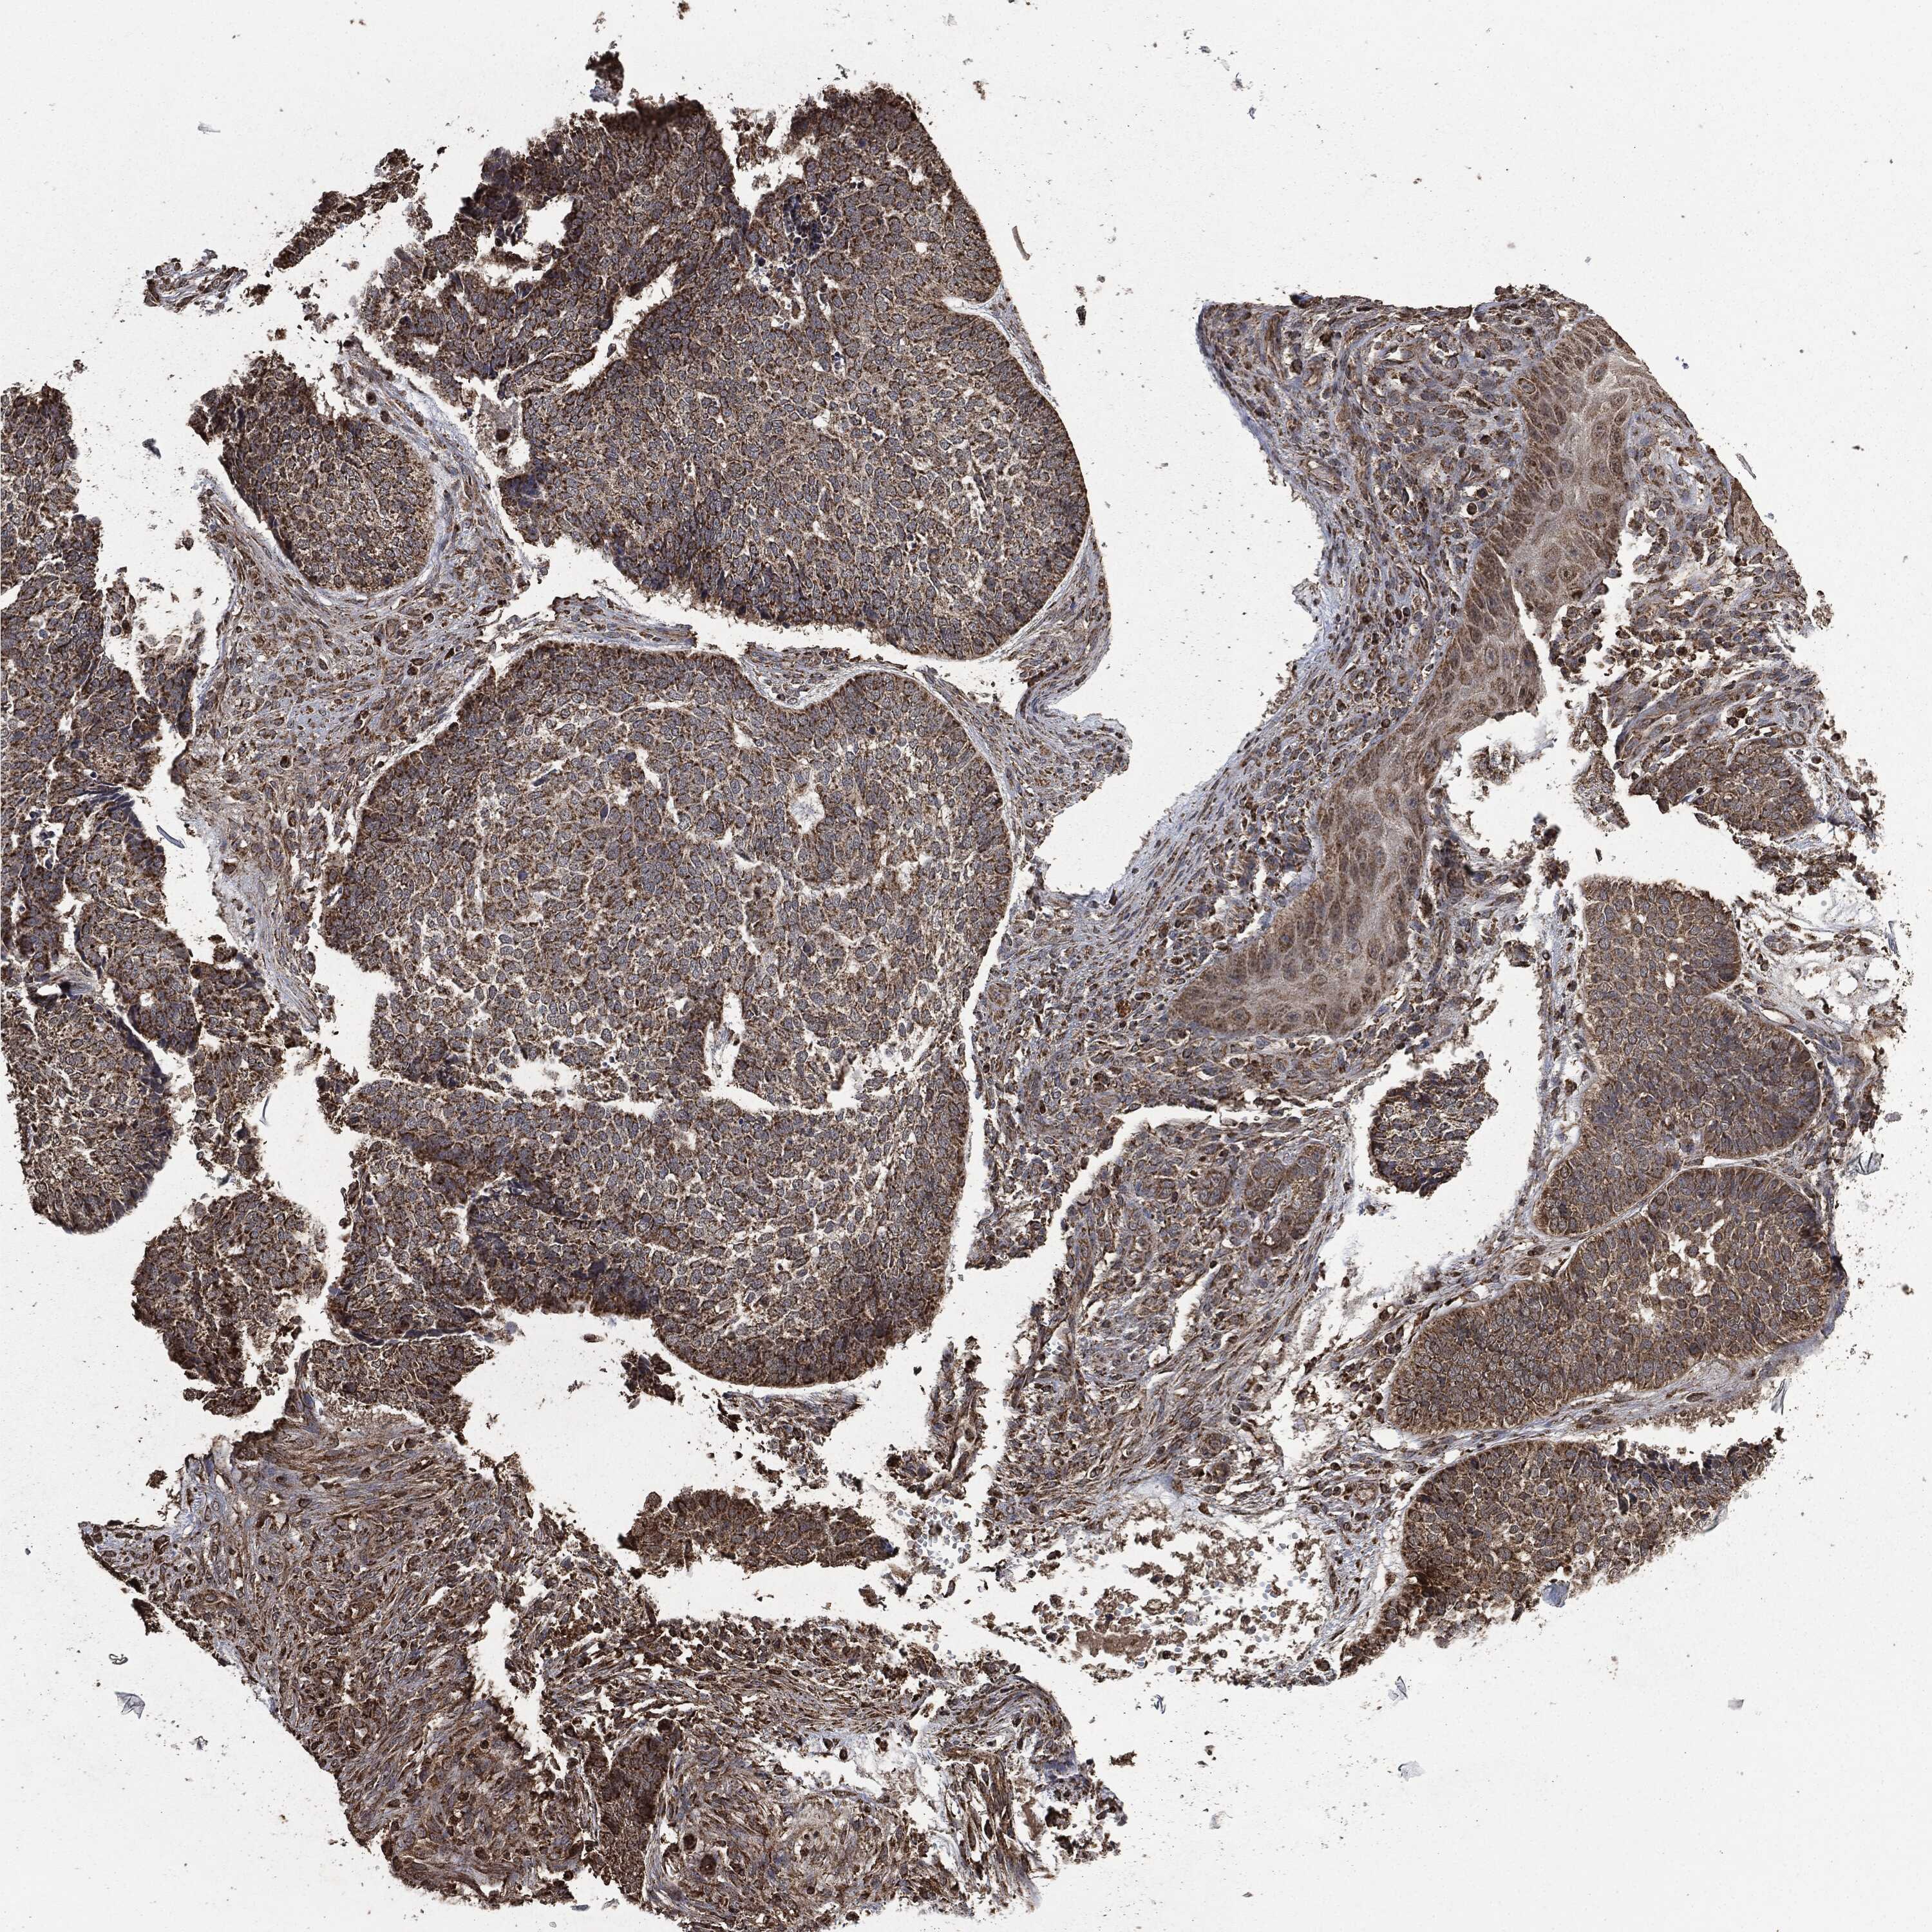

SKIN CANCER - Protein expressioni

A mouse-over function shows sample information and annotation data. Click on an image to view it in a full screen mode. Samples can be filtered based on level of antibody staining by selecting one or several of the following categories: high, medium, low and not detected. The assay and annotation is described here.

Antibody stainingi

Antibody staining in the annotated cell types in the current human tissue is reported as not detected, low, medium, or high, based on conventional immunohistochemistry profiling in selected tissues. This score is based on the combination of the staining intensity and fraction of stained cells.

Each image is clickable and will lead to virtual microscopy that enables deeper exploration of all samples and also displays staining intensity scores, fraction scores and subcellular localization as well as patient and tissue information for each sample.

Antibody HPA006723

Antibody CAB080348

Staining

High

Medium

Low

Not detected

Intensity

Strong

Moderate

Weak

Negative

Quantity

>75%

75%-25%

<25%

None

Location

Nuclear

Cytoplasmic/membranous

Cytoplasmic/membranous,nuclear

Squamous cell carcinoma, NOS

Squamous cell carcinoma, metastatic, NOS

Basal cell carcinoma

Papilloma, NOS